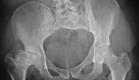

Metal-on-metal hip replacements may cause more pseudotumors

Dutch researchers recently revealed that patients with metal-on-metal total hip replacement systems may be at a 10 percent greater risk for developing pseudotumors.

fractured femur